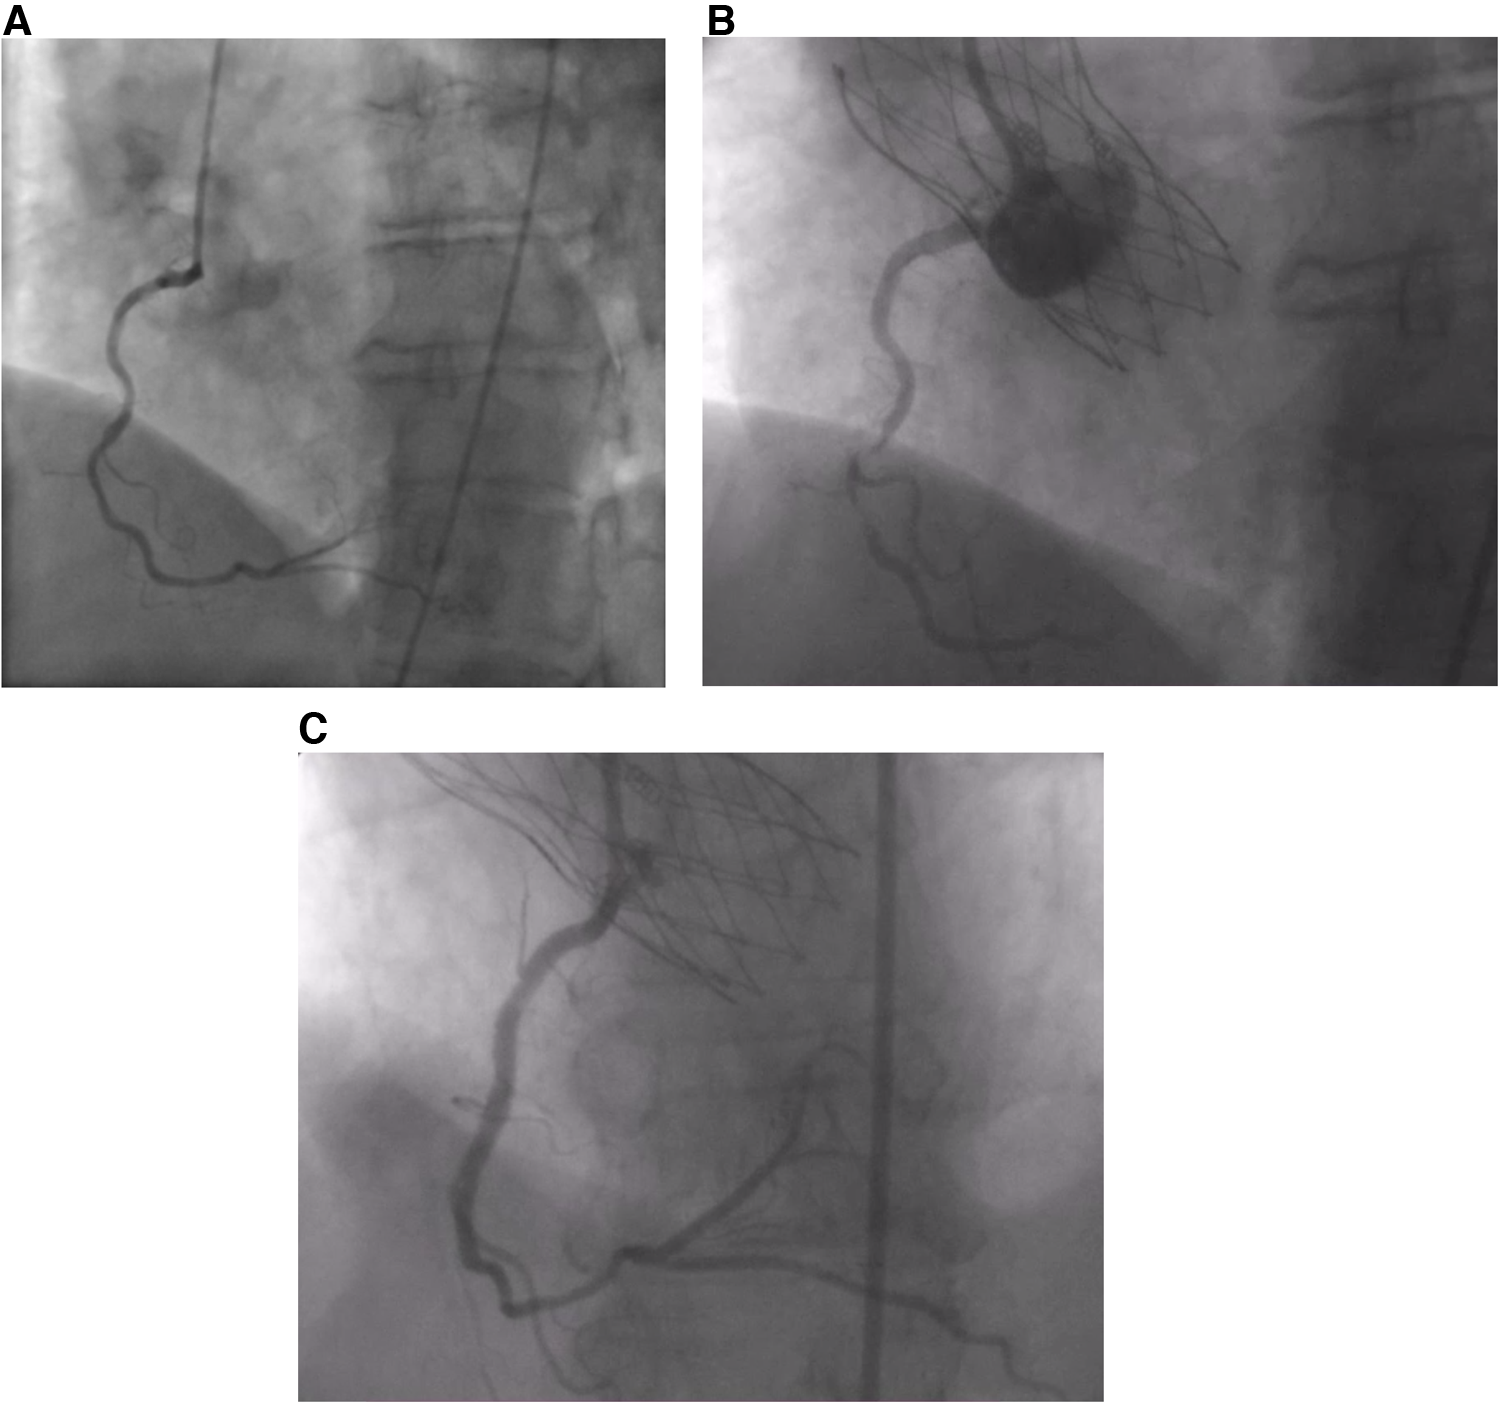

Figure 1

(A) Absence of CAD prior to the procedure. (B) Thrombus in RCA post-TAVI. (C) RCA post-stenting.

A 68-year-old female patient was referred to our institution for AS. She has a past medical history of hypertension and hypothyroidism as well as a recent diagnosis of urothelial carcinoma. She is a chronic smoker with a 30-pack-year history. Routine transthoracic echocardiography (TTE) reported a left ventricular ejection fraction of 60%–64% and a calcified aortic valve with a mean gradient (MG) of 40 mmHg and an aortic valve area of 0.8 cm2. Virtual basal ring sizing showed a perimeter of 70.2 mm2 with an area of 378.4 mm2 and a sinutubular junction of 24.6 mm. Pre-procedural cardiac catheterization showed non-obstructive coronary artery disease (Figure 1A). Further assessment with computed tomographic (CT) angiography demonstrated atherosclerotic calcifications of the aortic root, thoracic aorta, and coronary arteries and an incidental kidney tumor. Consequently, the heart team opted for TAVI given her need to undergo an urgent nephrectomy for her urothelial carcinoma.

She was doing well until 10 days after the procedure when she presented with acute severe chest pain (Figure 2). Immediate ECG showed evidence of inferior myocardial infarction (MI) with ST elevations in leads II and III and ventricular fibrillation (aVF). High sensitivity troponin level was elevated reaching 50,000 pg/ml. She also had an elevated c-reactive protein and white blood count; however, she did not have any fever or positional chest pain. Her blood pressure was 120/60 mmHg. TTE showed evidence of inferior wall hypokinesis. Emergent coronary angiography revealed a thrombus occluding the second segment of the right coronary artery (RCA) (Figure 1B). Angioplasty was performed with implantation of one drug-eluting stent (Figure 1C). The patient's symptoms, ECG changes, and troponin elevations provided evidence in favor of MI instead of other differentials such as pericarditis or aortic dissection following the procedure. She was stabilized and discharged on 75 mg of clopidogrel, 100 mg of aspirin, 5 mg of amlodipine twice daily, and 2.5 mg of bisoprolol twice daily.